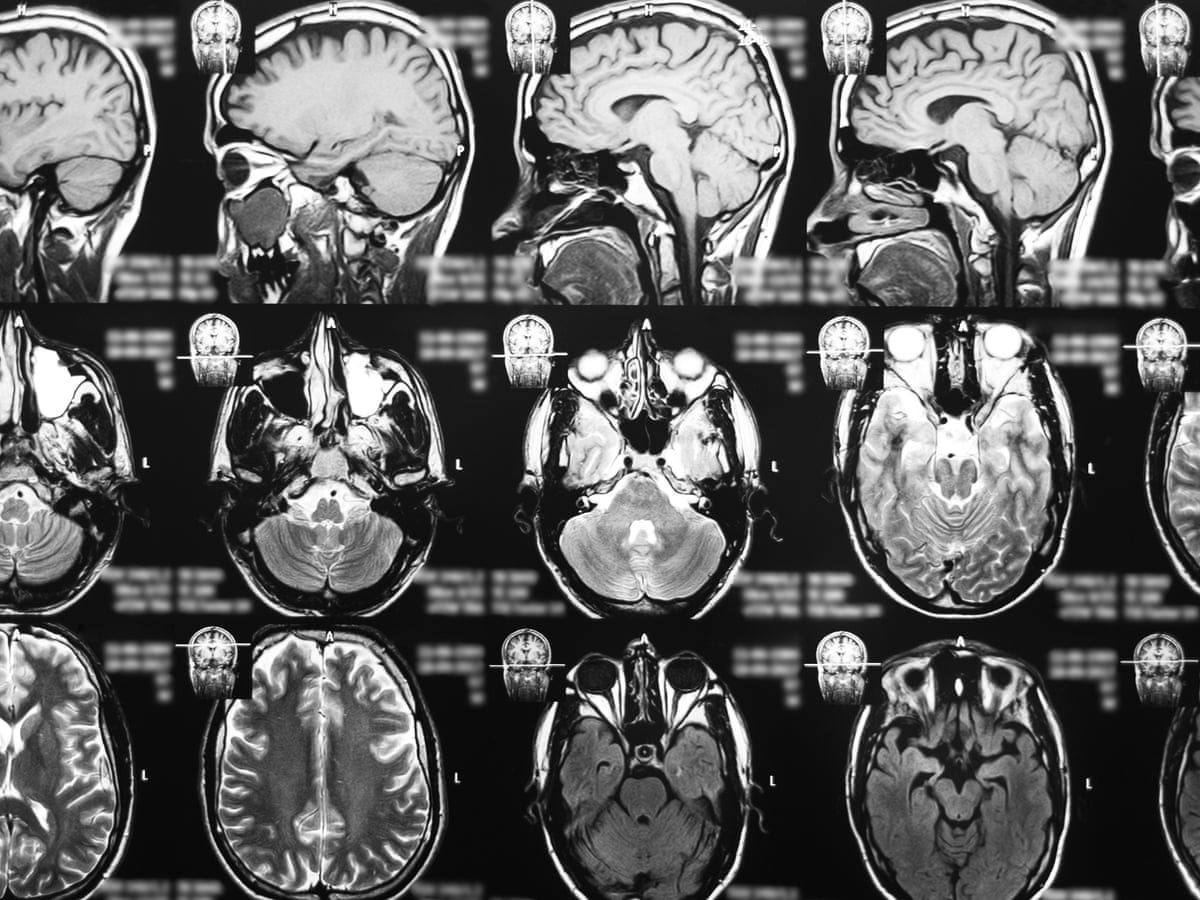

22072020 Objective assessments of brain function can help pinpoint when neurocognitive symptoms begin to appear in COVID-19 patients which patient groups are at a higher risk how long neurological.

27042021 In a postmortem brain from a person with COVID-19 a clotting protein called fibrinogen red indicates that the blood vessels are damaged and leaky. 28062021 Using single-cell RNA sequencing the researchers studied brain tissue samples from eight patients who died of COVID-19 and 14 controls who died of other causes. About one-third of COVID-19 survivors suffer from a variety of symptoms long after they were first infected.

04062020 And thanks to a new research consortium of more than 20 institutions including the University of Pittsburgh Medical Center New York University Johns Hopkins and health systems in Europe researchers including Stevens are using imaging and tests of blood and spinal fluid to understand how the coronavirus operates so they can prevent and treat effects on the brain. Their findings reveal the drug not only prevents people from contracting COVID. 19022021 While the path to finding a scientific treatment for COVID brain fog is yet to be determined experts suggest investing in activities that lead to mental calm and peace.

Respiratory and gastrointestinal symptoms are accompanied by short- and long-term neuropsychiatric symptoms NPs and long-term brain sequelae. Give your brain the best chance to heal by avoiding substances which can. A study found that people who went on oxygen therapy for the virus had lower gray matter.

Loss of taste or smell is a common neurological symptom of COVID-19. 01112020 The faster such treatments are tested the better Stevens adds since some of the brain damage from COVID-19 may be irreversible. 20052021 Certain COVID-19 treatments might also lessen the volume of gray matter in the outer layers of the brain.